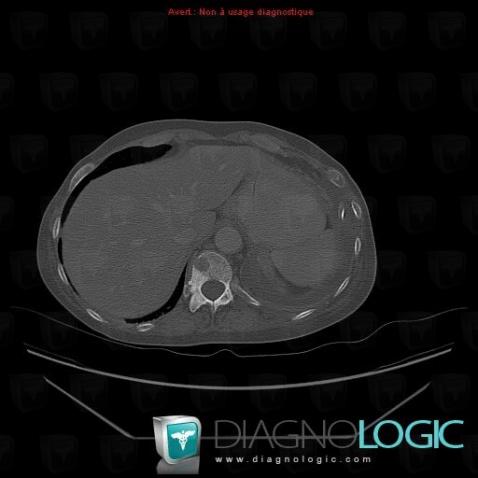

Metastasis, Ribs, CT

Here is the specific information in the key image above:

- Diagnosis Metastasis, Location(s) Ribs, with gamuts Sclerotic lesion of ribs